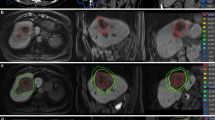

A retrospective study was conducted with 62 patients who received RT for liver cancer in Shandong Cancer Hospital from February 2022 to February 2023. This study was approved by the Ethics Review Committee of Shandong Cancer Hospital (SDTHEC2022012021), and informed consent was obtained from all patients and their families. To better describe the relationship between the plan and the location of the mass, the liver was divided into four quadrants (Fig. 1). According to the distribution of the portal vein and hepatic vein in the liver, anatomical segmentation and lobulation was carried out, generally dividing the liver into 5 leaves and 8 segments. The liver was divided into four quadrants: 1, 2, 4a as the I quadrant, 7, 8 as the II quadrant, 5, 6 as the III quadrant, and 3, 4b as the IV quadrant (Fig. 2).

Development and assessment of reference plans

The program evaluation was conducted by attending physicians and medical physicists using dose-volume histogram (DVH) indicators based on the same regimen. The uniformity and consistency of the dose in the target area were evaluated by the conformity index (CI) [19] and homogeneity index (HI) [20]. The dose distribution to the PTV and OARs was evaluated by average dose (Dmean), minimum dose (Dmin), maximum dose (Dmax) and Vx (percentage of volume accepted xGy). This study is normalized and compared with the percentage of the target dose of DVH in the corresponding prescription dose because the patients' tumor sizes, shapes, and prescription doses varied.